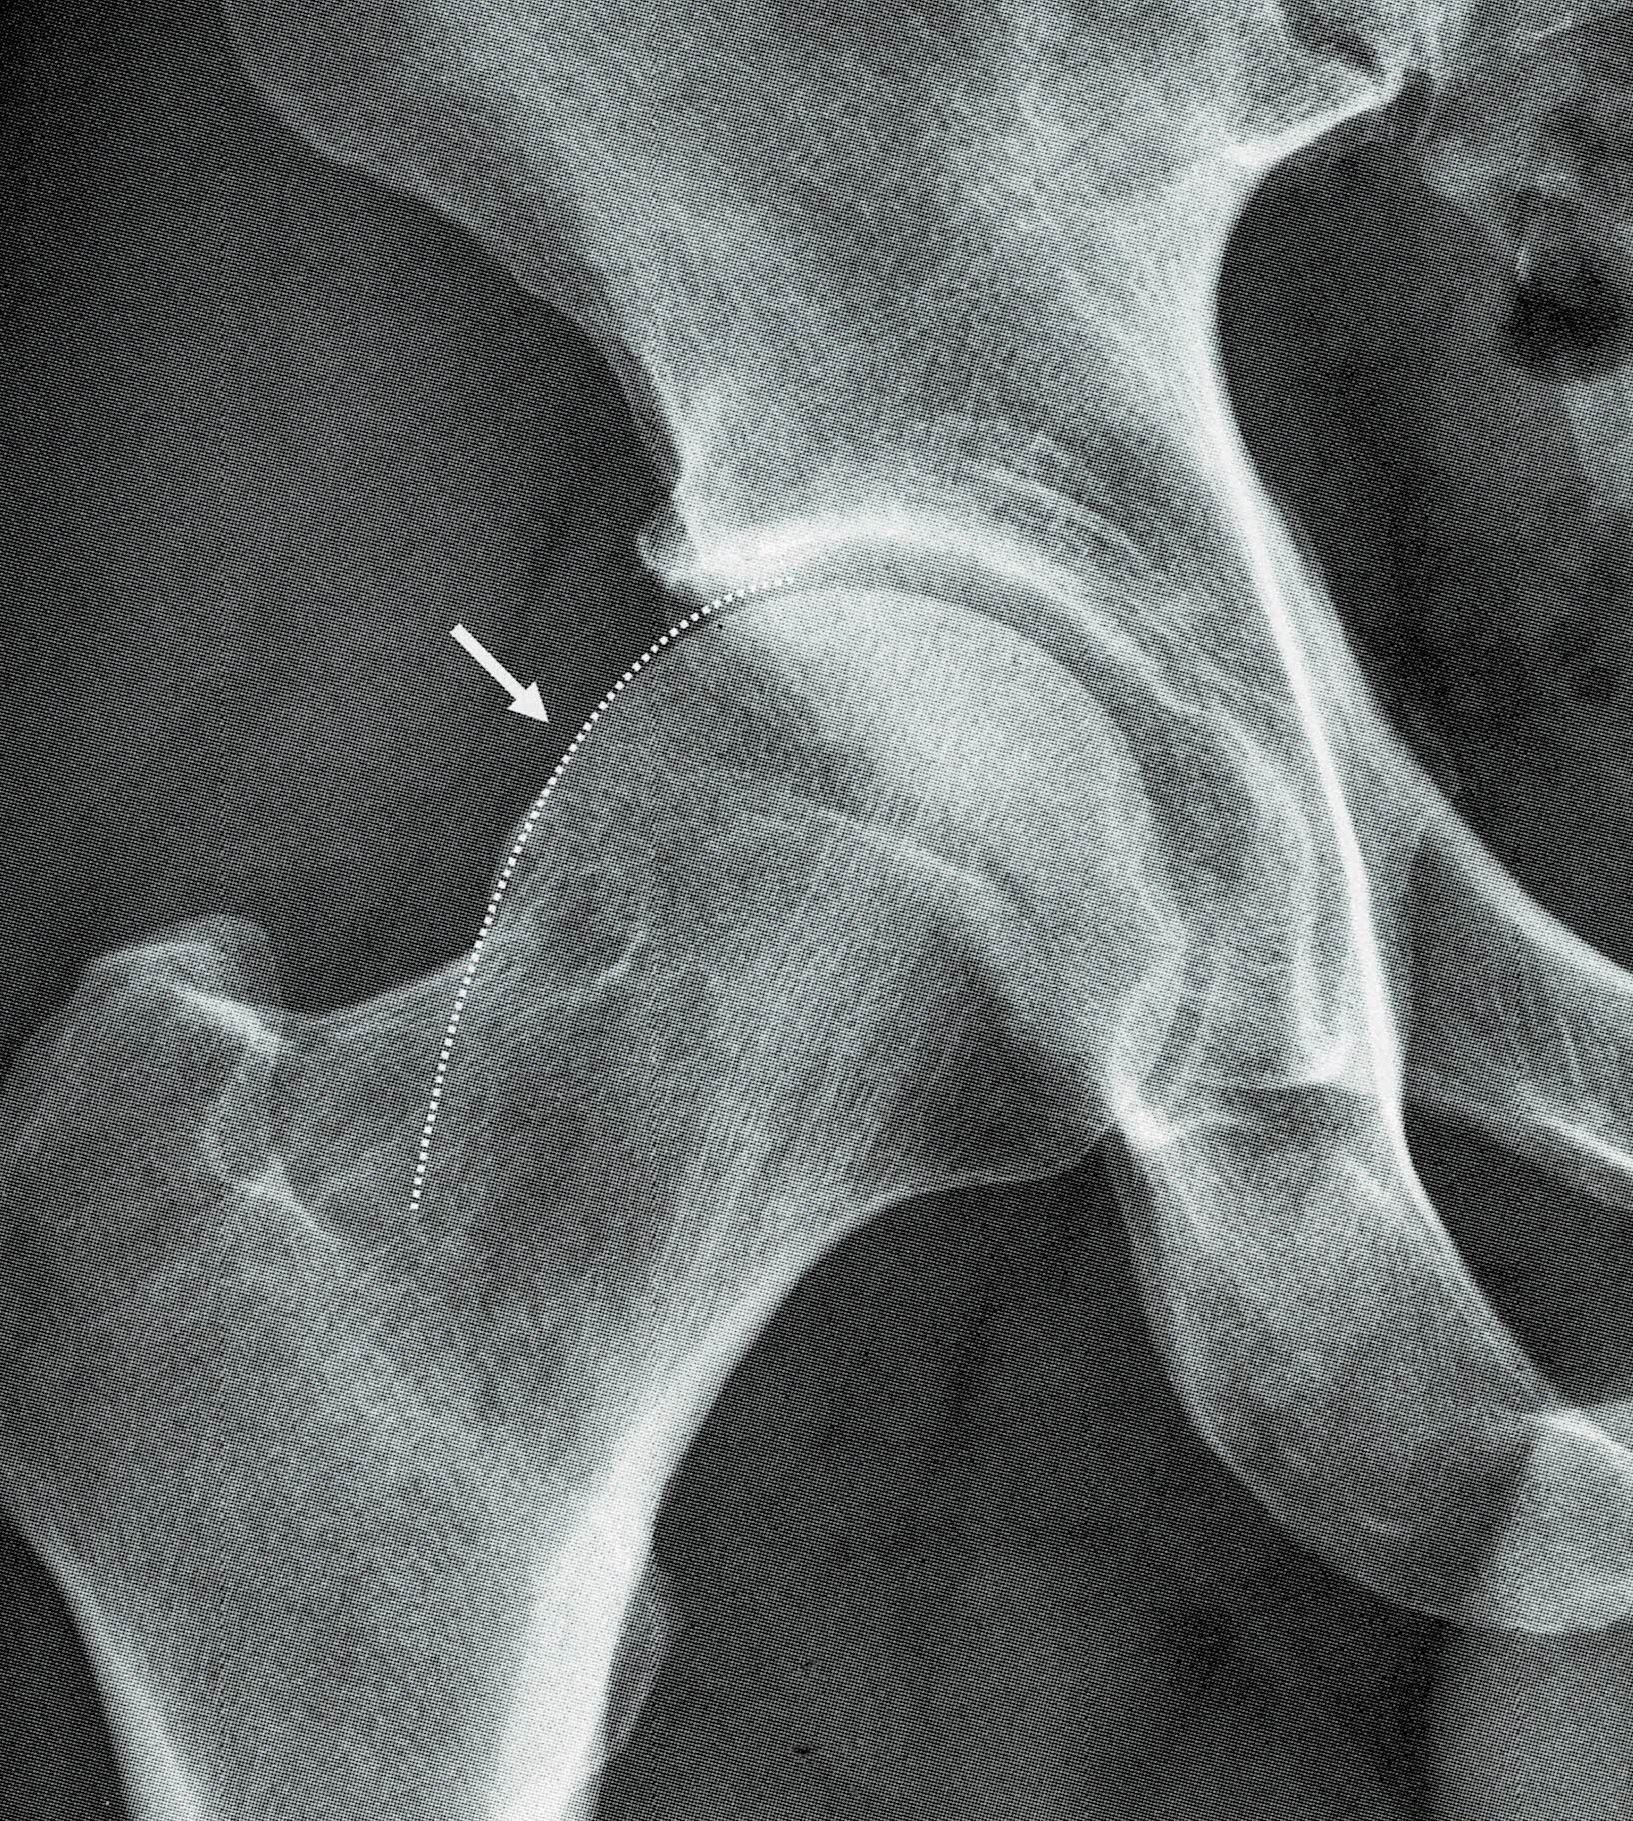

① 股関節インピンジメント(FAI)

骨の形がわずかに変形していることで、動かしたときに骨同士がぶつかる病気です。

② 臼蓋形成不全(きゅうがいけいせいふぜん)

股関節の受け皿が浅いため、骨頭をしっかり支えられず、関節に負担が集中します。